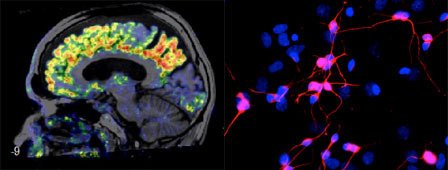

Foto: A. Varrone,L. Brundin,L. FardeJohan Lundbergs forskargrupp

Molekylär hjärnavbildning, neuropsykofarmakologi, depressions- och ångestsjukdomar